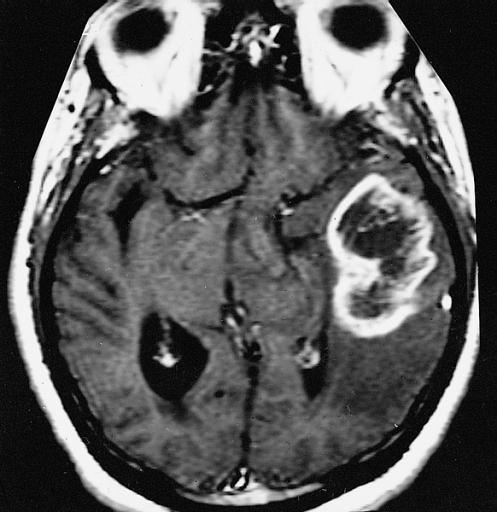

Glioblastoma multiforme. (Foto: Armed Forces Institute of Pathology)